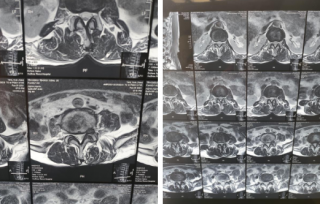

科室选派医生到北京、上海、苏州等重点医院进修,开展各类脊柱疾病颈腰腿疼痛疾病的诊疗和腰椎管狭窄、腰椎间盘突出症、腰椎间盘源性疼痛、脊柱侧弯、脊柱骨折等脊柱手术,积累了丰富的临床经验。

• 1、微创经椎间孔椎体融合术(MIS-TLIF)

• 2、颈椎前路椎间盘摘除融合内固定术(ACDF)

• 3、显微镜下髓核摘除术

• 4、微创脊柱内镜下髓核摘除术

• 5、天玑骨科机器人辅助下全脊柱微创手术